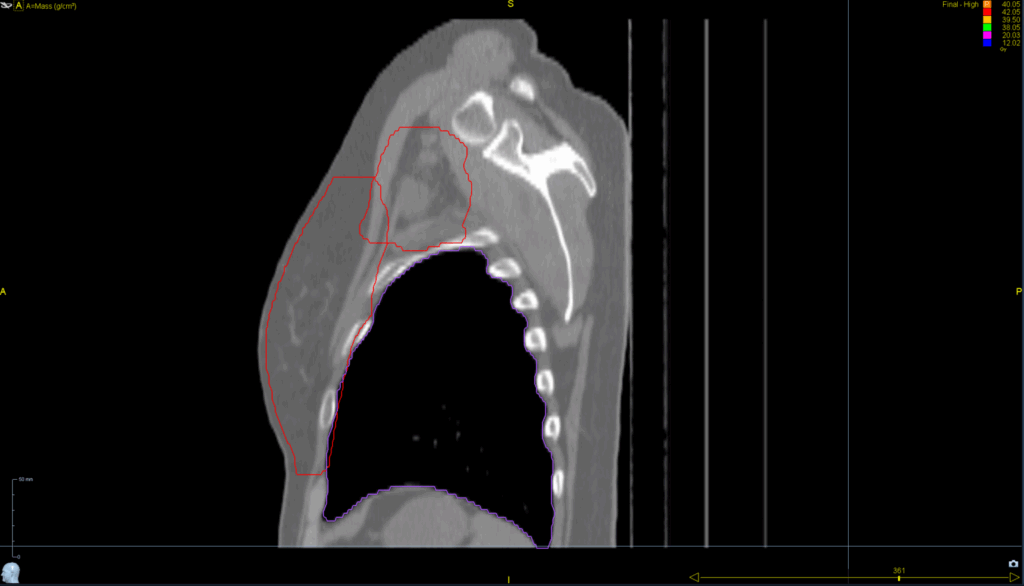

Planning CT Images

Treatment Plan Images